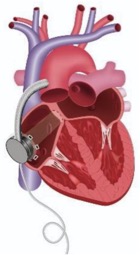

由于左心室腔较小,采用改良技术植入LVAD,通过左心房提供支持。通过右心房切开术,植入一根由20 mm Gore-Tex®插入式移植物制成的导管,一端缝入已形成的房间隔缺损,另一端用LVAD的缝合环缝入右前房壁。然后将HeartWare™HVAD™流入套管插入右心房壁的Gore-Tex®移植物中,并固定在缝合环上(图1)。修剪流出的移植物并与升主动脉吻合。三尖瓣后叶在相邻连合处缝合。左心耳未闭合。手术结束时,HVAD固定在胸腔右侧,然后胸腔闭合(图2和图3)。术后,患者在重症监护病房(ICU)接受护理,并于术后第二天(POD)拔管。患者于POD7转出ICU和高度依赖病房,于POD 21出院。

图2. 胸部X光显示LVAD泵位于右心房前方的位置

图3. 图示LVAD如何通过右心房切开术植入并连接缝合到患者房间隔的Gore-Tex®移植物导管